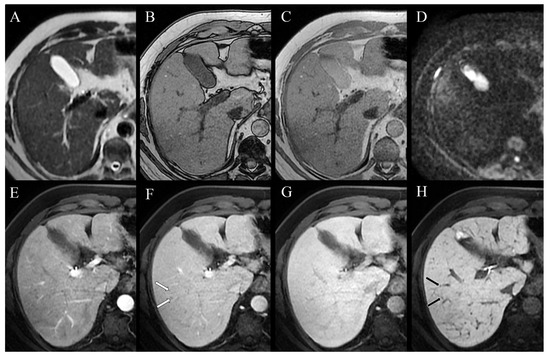

2. Case Presentation